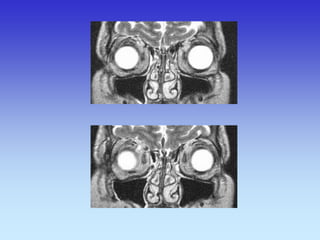

Rectus Medialis

Rectus Lateralis

Inferior Turbinate

Frontal Lobe Rectus Superior Rectus Inferior Maxillary Sinus Tooth